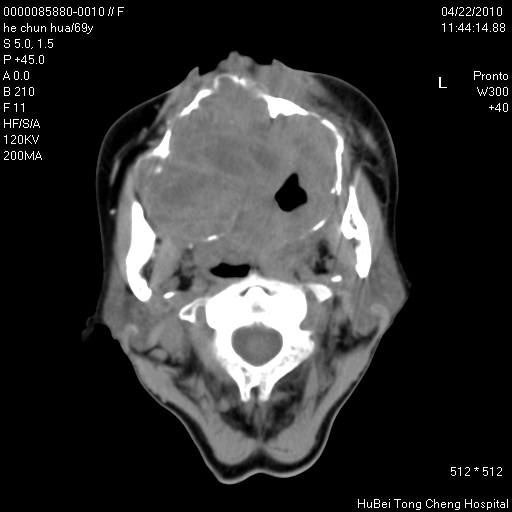

标题: CT25937:女,69Y

硬腭部包块十余年,渐进性增大。

硬腭占位 恶性可能性大

骨源性肿瘤 造秞细胞瘤

考虑硬腭部肿瘤恶变,gcrg可能,鉴别于gct。